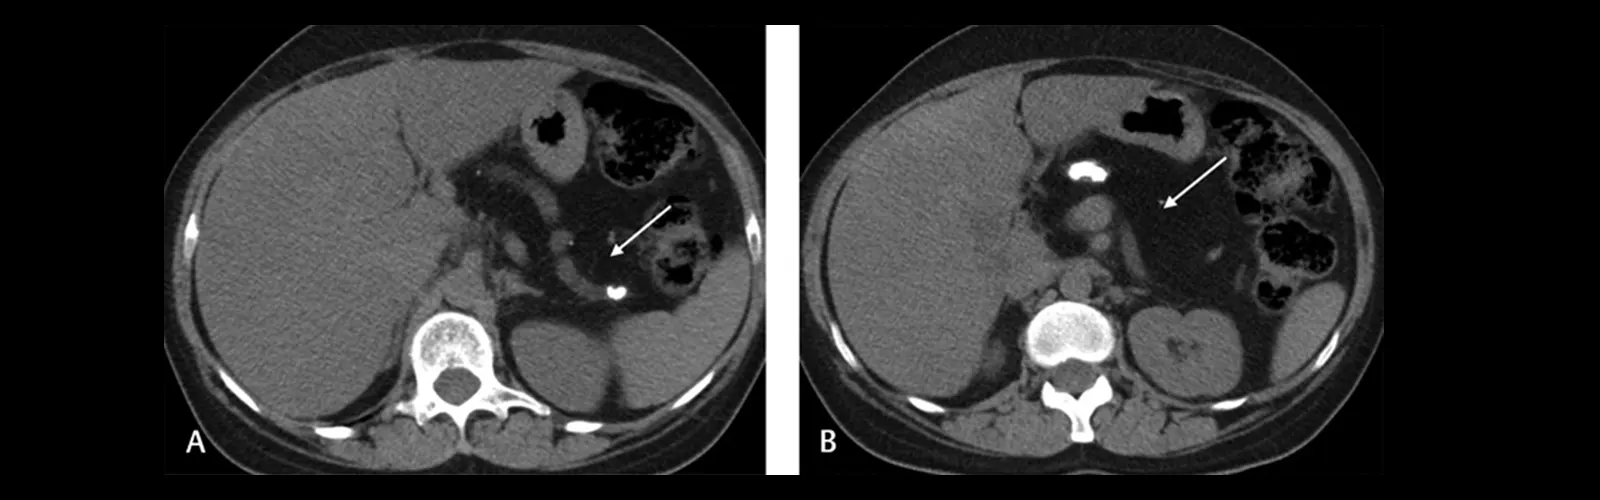

It is used to create exact pics of the stomach organs, such as the liver, pancreas, and kidneys.